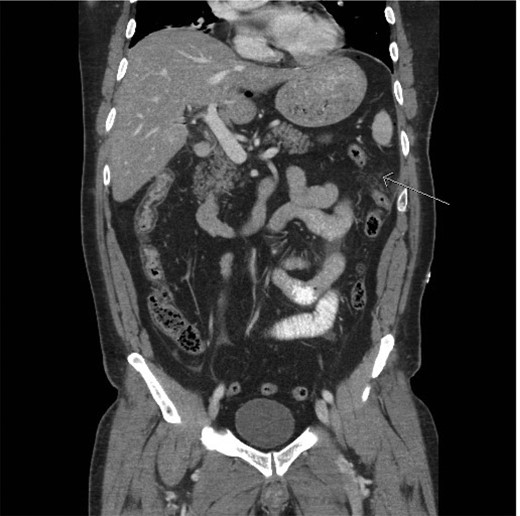

A CT scan demonstrated significant soft tissue stranding/edema of the omentum in the left hemi-abdomen. In addition, there was mild ascites and multiple scattered locules of air (Figs 3–5). No other abnormality of the small or large bowel was identified. He was admitted for observation and broad-spectrum antibiotic therapy was initiated. On post admission day 2, he became diffusely peritonitic, febrile with a temperature of 39.1°C and his oxygen requirements increased to 12 l/min.

CT scan (frontal view) demonstrating stranding/edema to the omentum (arrow).

Our case demonstrates the diagnostic dilemma that accompanies delayed bowel injuries. Laboratory tests often give nonspecific results that seldom point to a diagnosis [1]. Imaging studies also fail to establish the etiology. Our CT scan failed to demonstrate significant intraperitoneal free air (Figs 3–5). In addition, oral contrast was utilized, but gross extravasation was not identified.